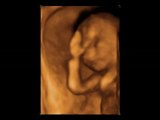

Anne karnında zafer işareti yaptı

4 Boyutlu Ultrason ile Anne Karnında Bebek Resimleri

Daha Anne Karnında Zafer İşareti Yaptı